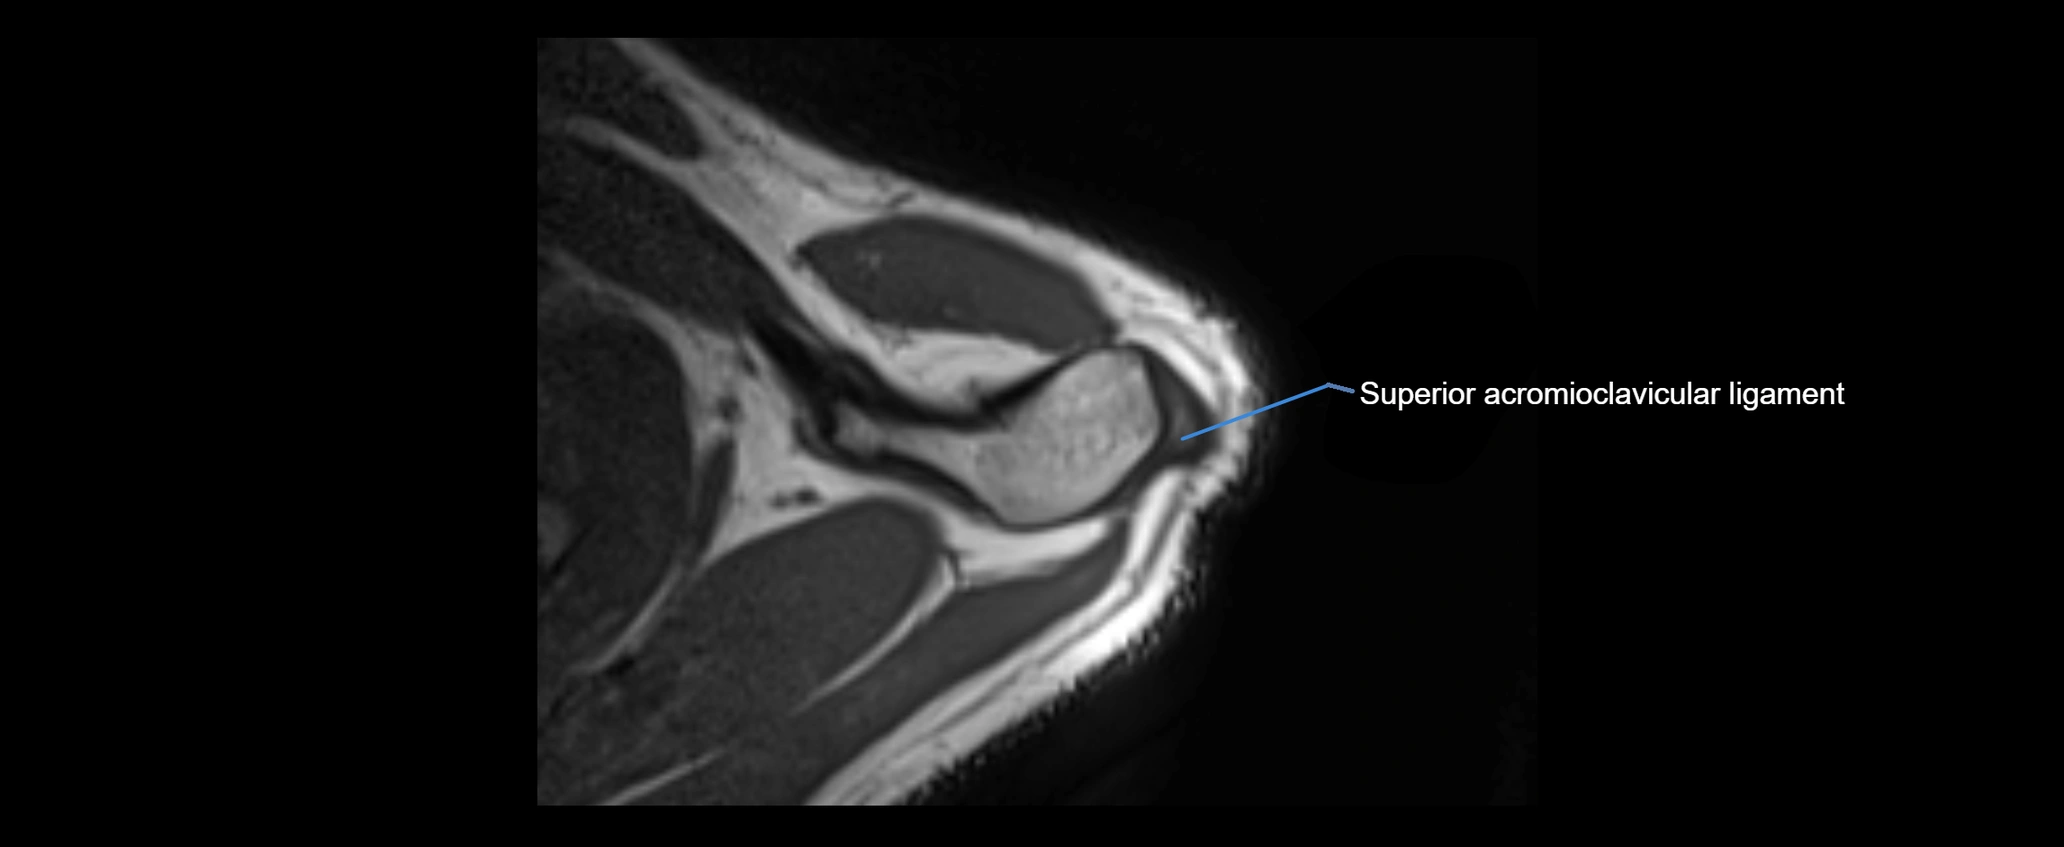

MRI images

image